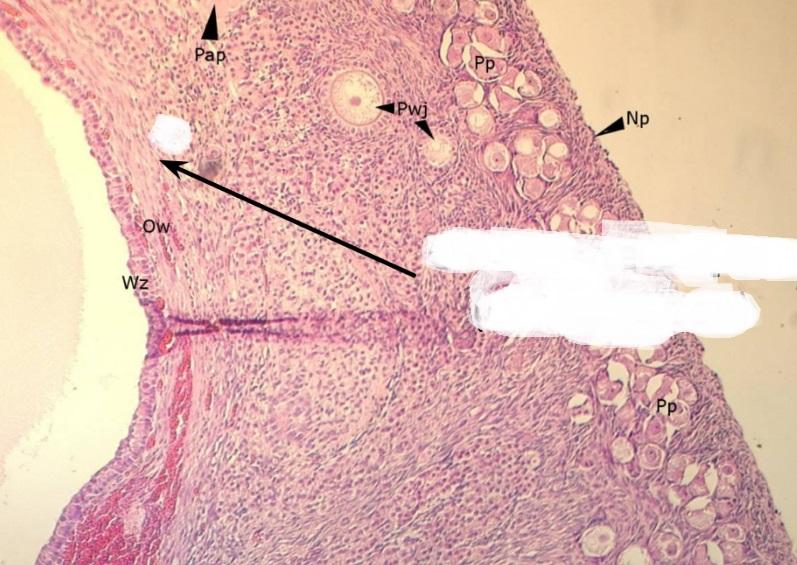

pęcherzyk wzrastający bezjamisty (jajnik, kora)

pęcherzyki dojrzewające jamiste (jajnik, kora)

pęcherzyk Graafa (jajnik, kora)

pęcherzyk atrezyjny (jajnik, kora)

błona biaława (jajnik, kora)

gruczoły śródmiąższowe (jajnik, kora)

warstwa ziarnista pęcherzyka (jajnik, kora)

osłonka wewnętrzna - obfita w komórki (jajnik, kora)

osłonka zewnętrzna - z dużą ilością włókien (jajnik, kora)